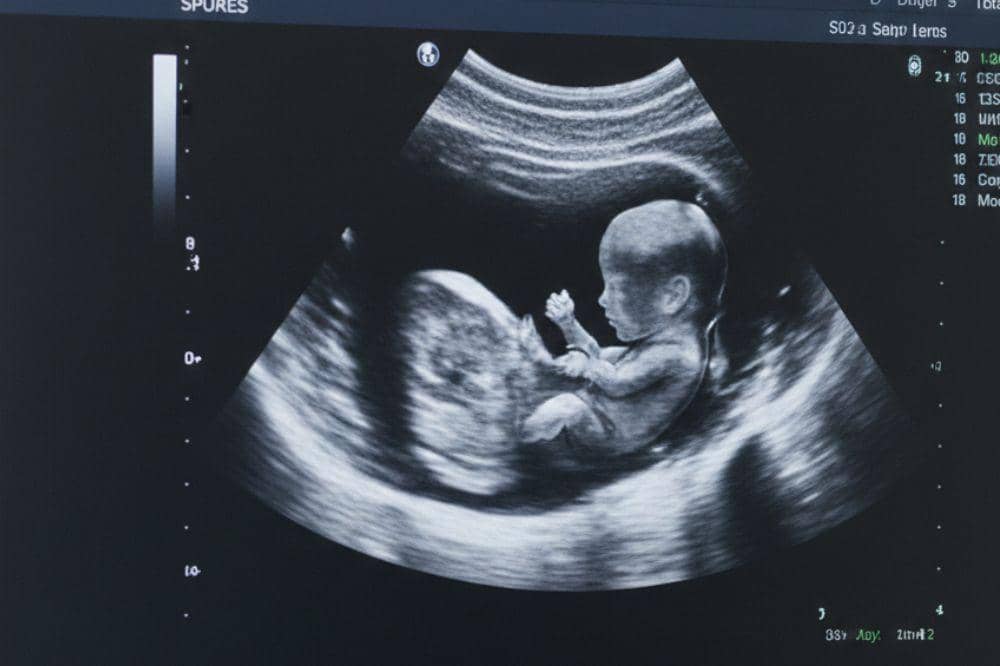

6. Periksa USG untuk mengetahui posisi janin lebih pasti

Untuk mengetahui letak janin dan posisinya di dalam perut secara lebih pasti, sebaiknya Mama melakukan pemeriksaan ultrasonografi (USG). Melalui pemeriksaan ini, dokter kandungan dapat melihat dengan jelas posisi janin, mulai dari letak kepala hingga arah tubuhnya, sekaligus memantau kondisi secara menyeluruh.